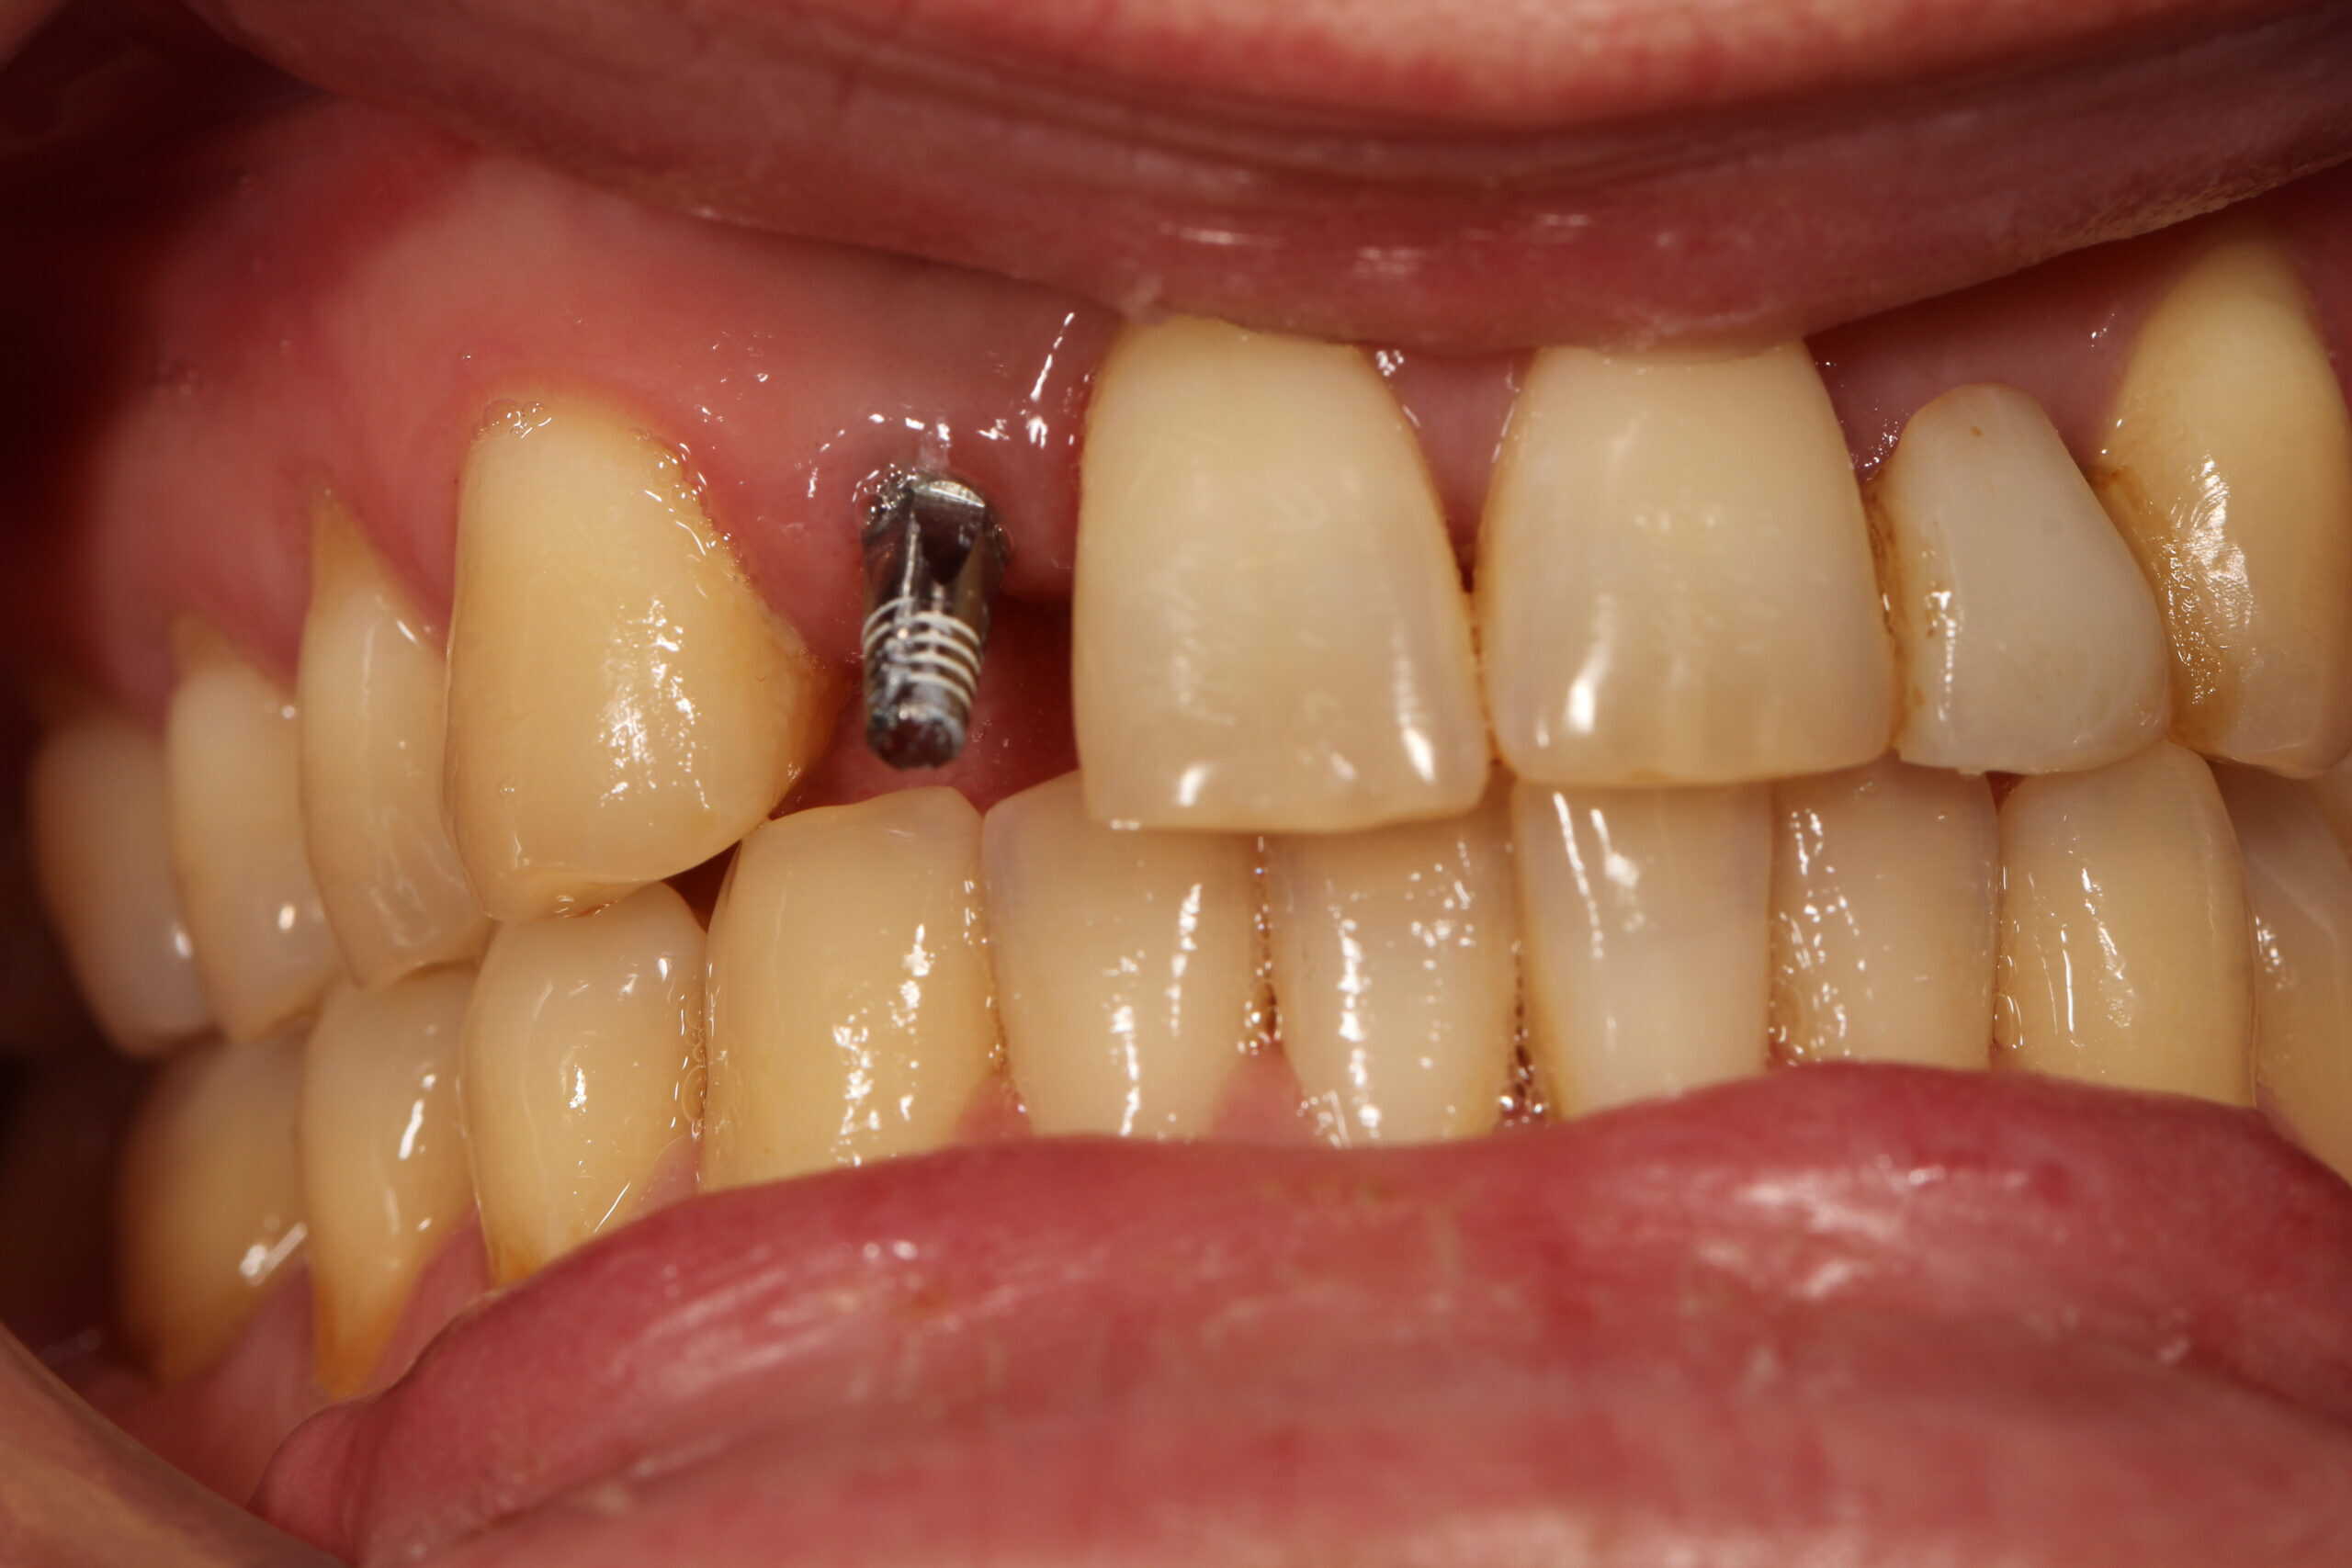

A narrow implant was Placed by Dr. Peter Mann.

Patient left the office with a temporary crown after his implant placement.